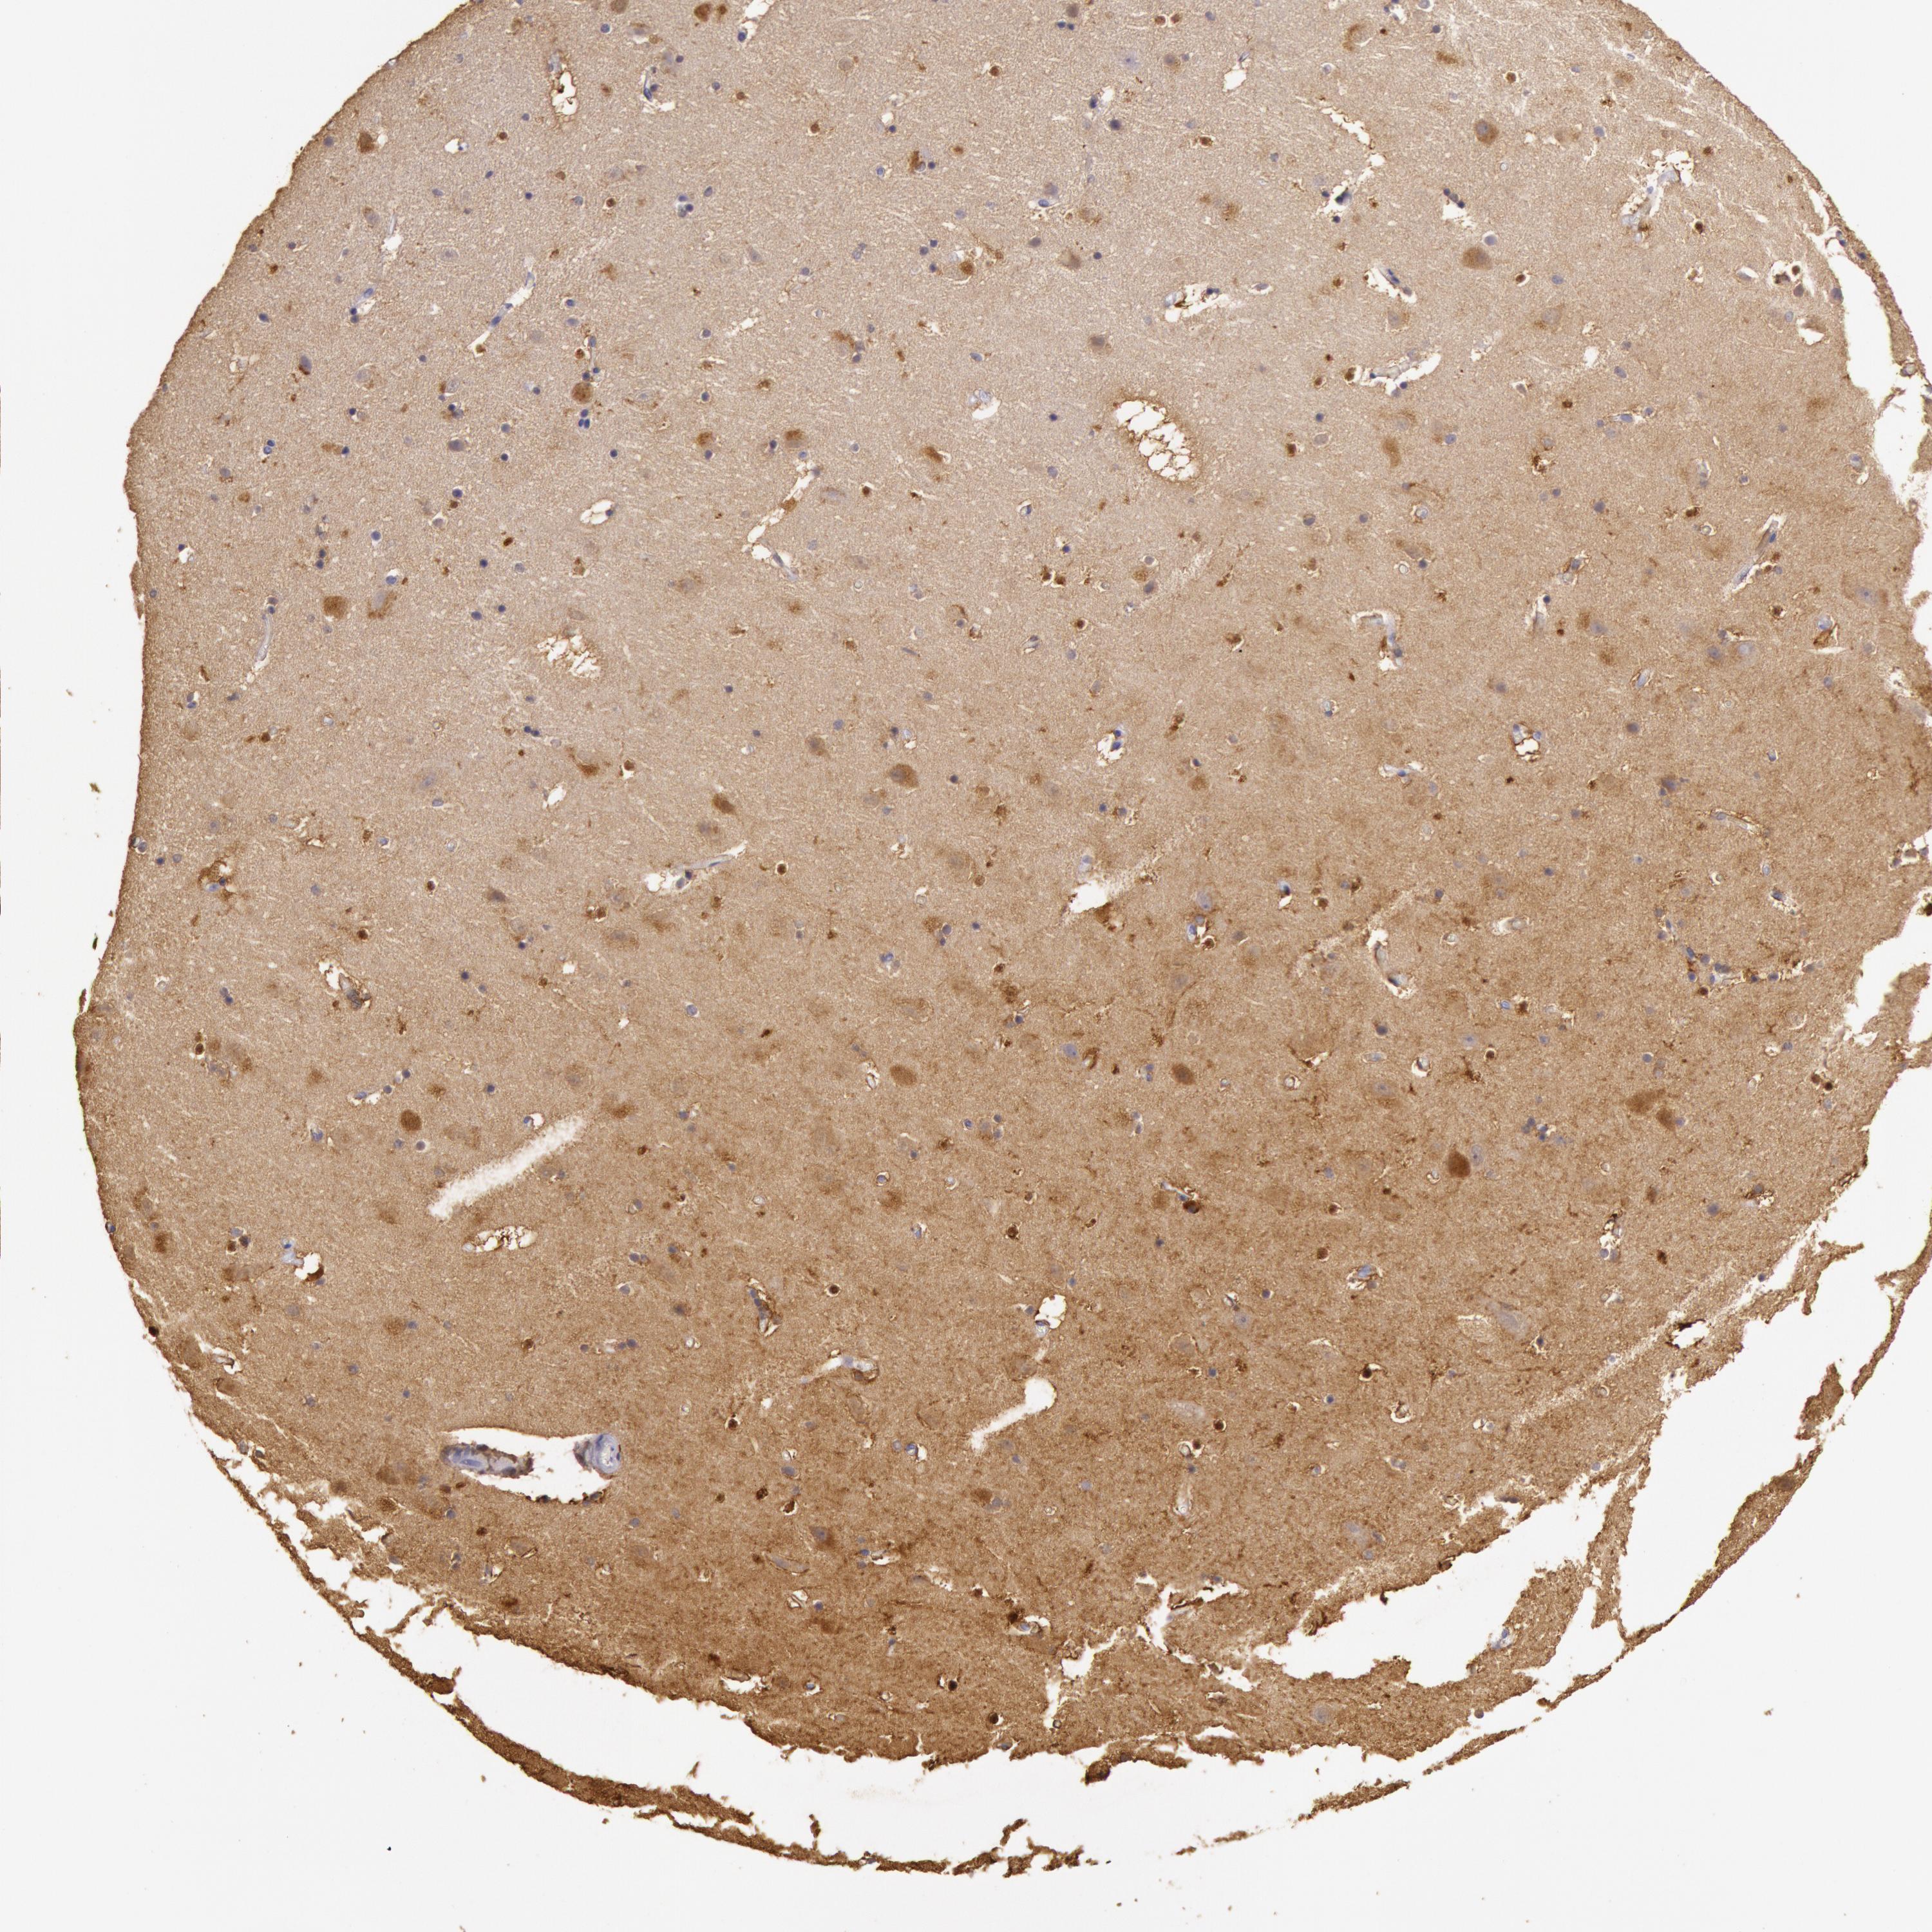

Antibody staining in the annotated cell types in the current human tissue is reported as not detected, low, medium, or high. This score is based on the staining intensity and fraction of stained cells.